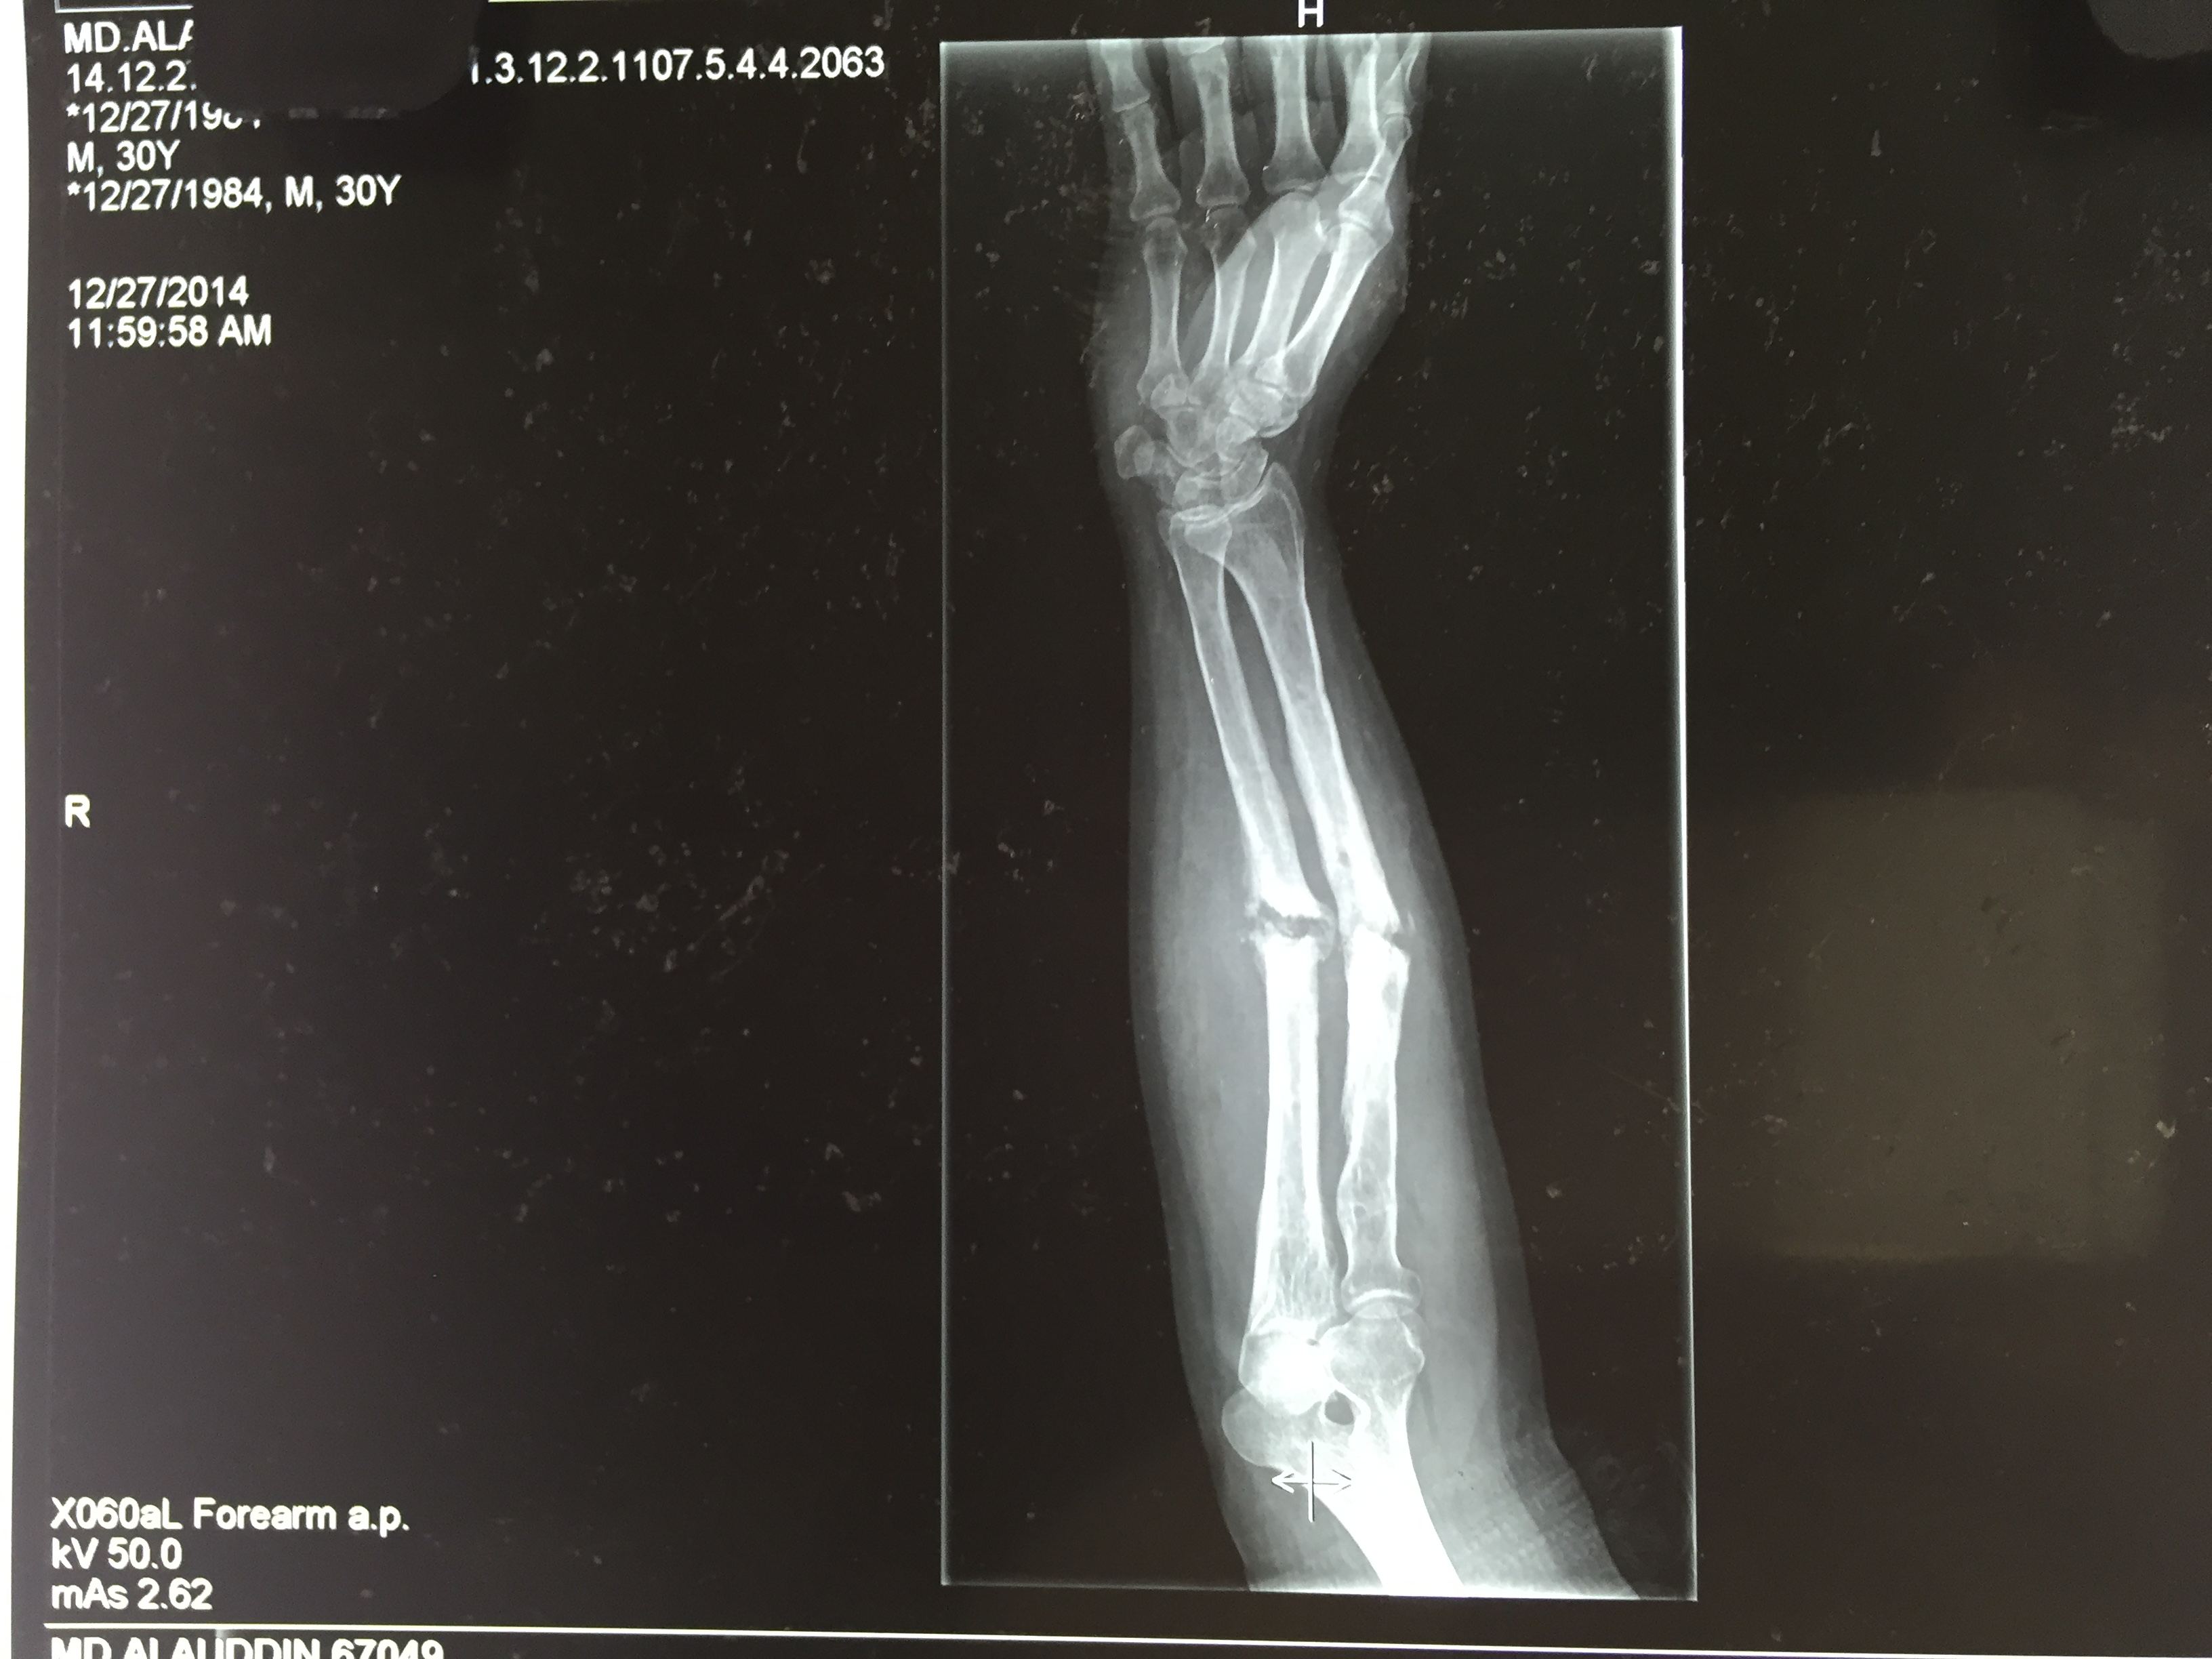

In order to determine the cause of a fracture, a doctor will inquire about the circumstances involved. A physical examination will then be performed to determine the cause. They will often order an X-ray and, in some cases, an MRI or CT scan in order to fully assess the fracture.